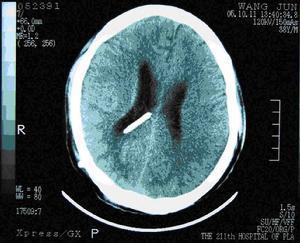

简单地说,就是在游泳池里加一个管道,把水引到下一级的水道里。现在更普遍的方式是脑室腹腔分流,也就是把脑室里的水引到腹腔里,腹腔有超强吸收能力的大网膜,这样就能把脑脊液的分泌和吸收重归平衡。图中脑内白色的短线就是分流管。

这个管子应该在脑积水早期放,此时患儿的头还不太大。如果头太大了,不仅要放管子,可能还要做头颅重塑。

下图就是我们科很久以前做的一例巨颅重塑术,当时还上了央视新闻,简单的说是将多余的颅骨打碎再重塑成可接受的造型。

术前

术后